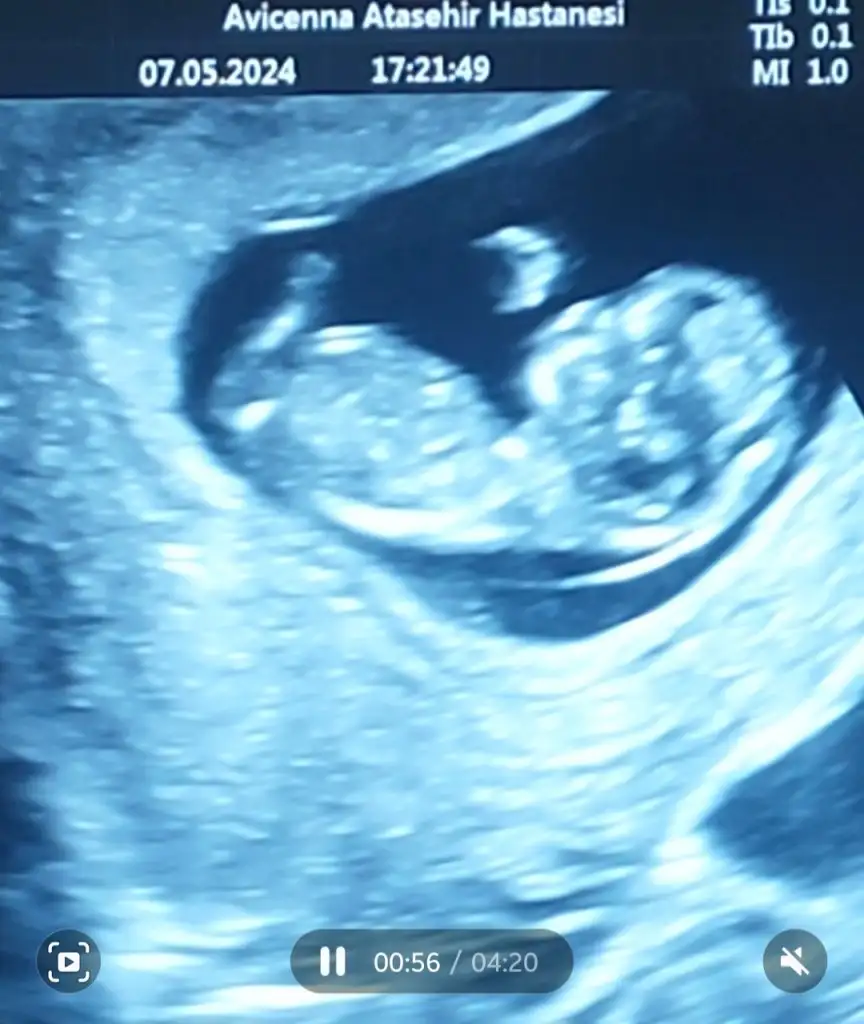

Kız gibi canımBenimkine de bakar mısınız10+2

Kız gibi canımBurda 10 haftalığız